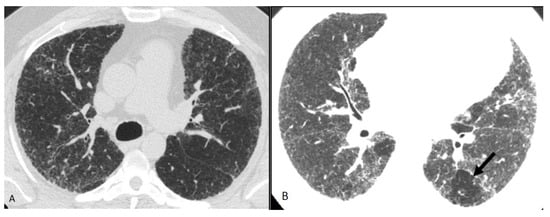

Three categories of NFHP (Table 3, Figure 8) and FHP (Table 4, Figure 9, Figure 10, Figure 11 and Figure 12) have been described.

Figure 10. Compatible with fibrotic HP. Axial and coronal expiratory phase CT (A,B) shows coarse reticulations and minimal traction bronchiectasis superimposed on extensive upper lung predominant GGOs with peribronchovascular and subpleural distribution. Air trapping (arrows) is evident.

Figure 11. Compatible with fibrotic HP. Inspiratory phase CT (top row) shows ground glass opacities and subtle fibrosis. Note the variant upper lung predominant distribution. Expiratory phase CT (bottom row) shows air trapping (arrows).

Figure 12. Compatible with fibrotic HP. Axial inspiratory phase CT shows (A) variant pattern of lung fibrosis with diffuse reticulations superimposed on a background of GGO and (B) lobular air trapping (arrow).